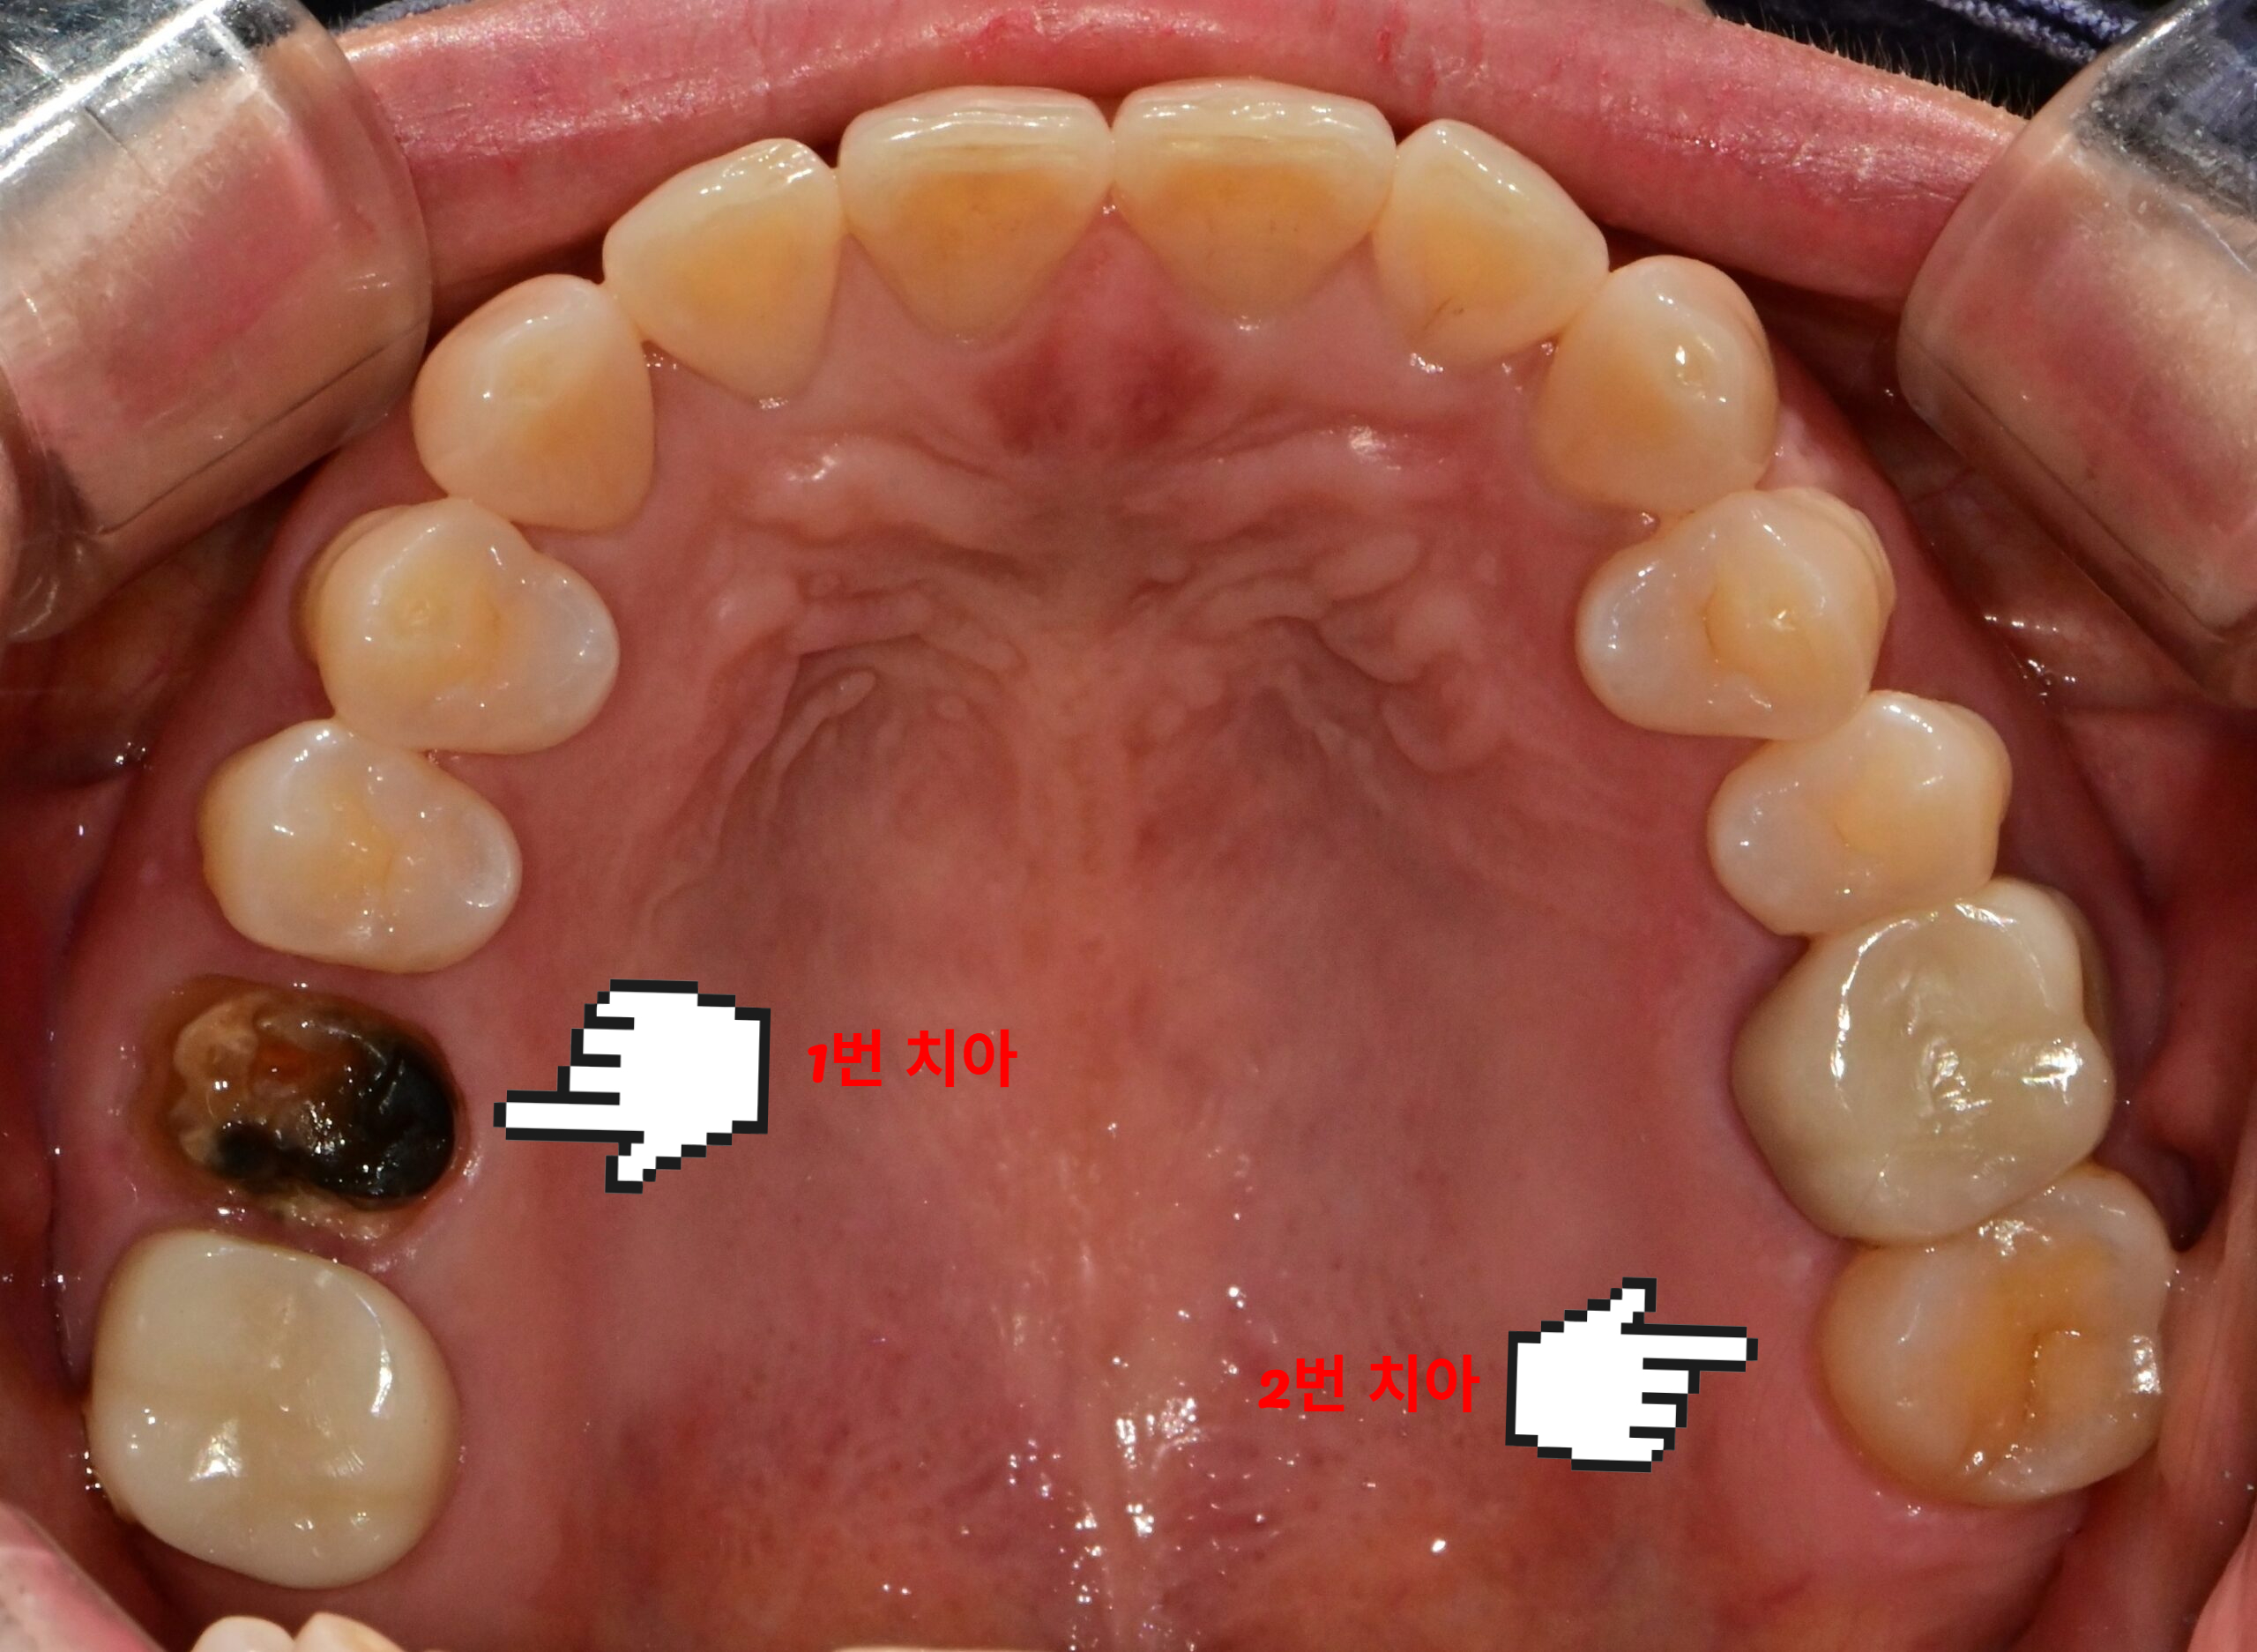

오래된 아말감 교체 전 다수의 아말감 충전 상태 구강 임상사진